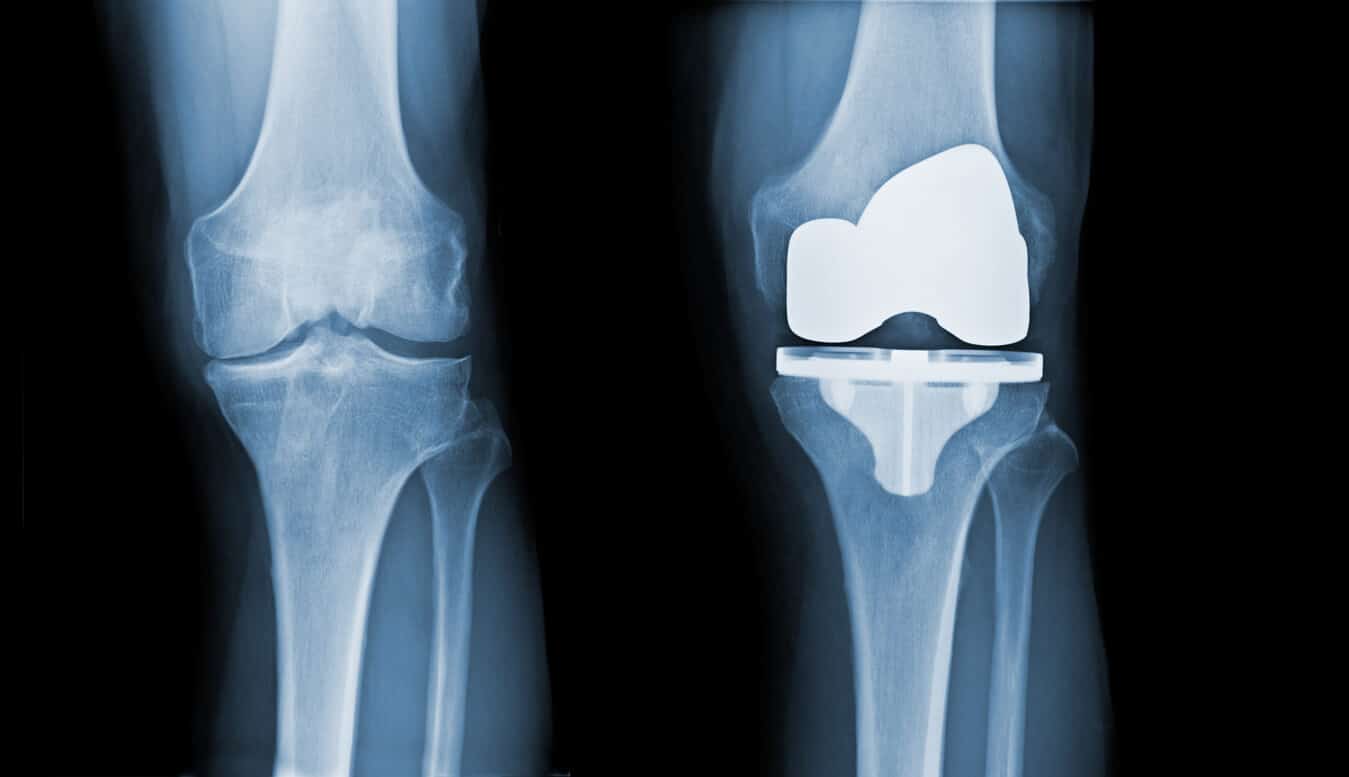

Knee replacement implants have multiple parts, including a liner. The liner goes between parts of the implant.

When you get joint replacement surgery — whether it is for a knee or hip — it is supposed to last for decades.

Because many thousands of these devices have been implanted, it’s possible the legal cases may number in the thousands. The number of complaints has continued to rise as patients who receive the recall notice go to their doctors for evaluation. These patients are given X-rays, MRIs — and even a procedure called an aspiration — to evaluate the state of their Exactech knees. From the procedure results, patients are learning their prosthesis has loosened, the inserts have degraded and shredded, there is polyethylene debris in the fluid around the knee, and that they need revision surgeries.